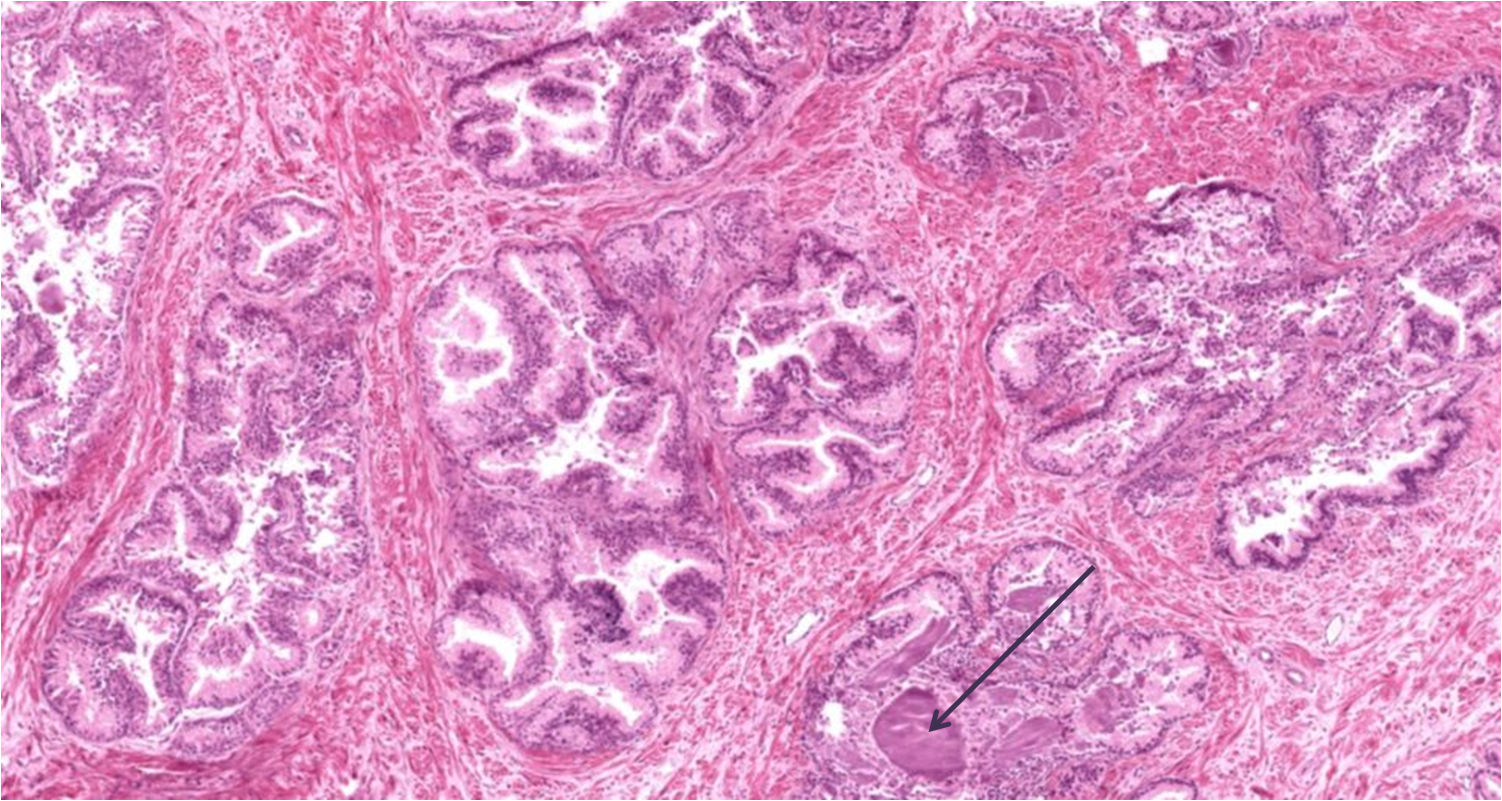

Próstata

Concreções prostéticas